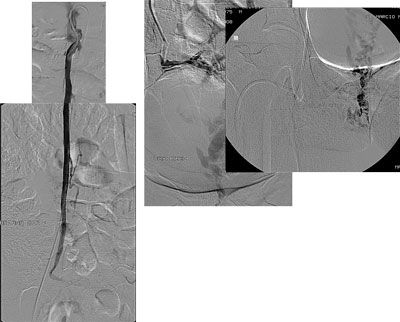

Paciente de 32 anos, feminino, nulípara, procurou consultório com queixa de fadiga nos membros inferiores e varizes vulvares que desciam até a face posterior da coxa direita. Realizado ultrassonografia com Doppler colorido de membros inferiores que mostrou normalidade das veias safenas e do sistema venoso profundo e identificou que as varizes da coxa direita corriam em direção a região genital. Solicitado ultrassonografia endovaginal com Doppler colorido que mostrou varizes pélvicas, sendo de maior calibre junto aos anexos à direita, com diâmetro máximo de 8 mm. A paciente foi submetida a flebografia que mostrou refluxo da veia ovariana direita com progressão do meio de contraste até a vulva. Realizado embolização da veia ovariana direita distalmente com polidocanol 3% para oclusão das colateriais pélvicas e com molas e histoacryl ao longo do seu tronco principal. A flebografia de controle mostrou oclusão completa da veia ovariana direita. Após 30 dias a paciente foi submetida à cirurgia convencional de varizes de membros inferiores através de mine-incisões da pele. Não houve intercorrências relacionadas ao procedimento endovascular e cirúrgico. No seguimento de 10 meses a paciente encontra-se assintomática e sem novas varizes, apresentando telangectasias residuais.